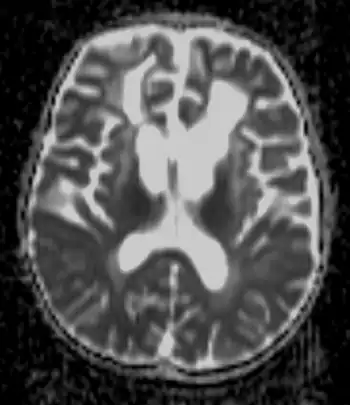

Detecting the signs of Alexander disease is possible with magnetic resonance imaging (MRI), which looks for specific changes in the brain that may be tell-tale signs for the disease.[11][12] It is even possible to detect adult-onset Alexander disease with MRI.[10] Alexander disease may also be revealed by genetic testing for its known cause.[13][14] A rough diagnosis may also be made through revealing of clinical symptoms, including enlarged head size, along with radiological studies, and negative tests for other leukodystrophies.[8]